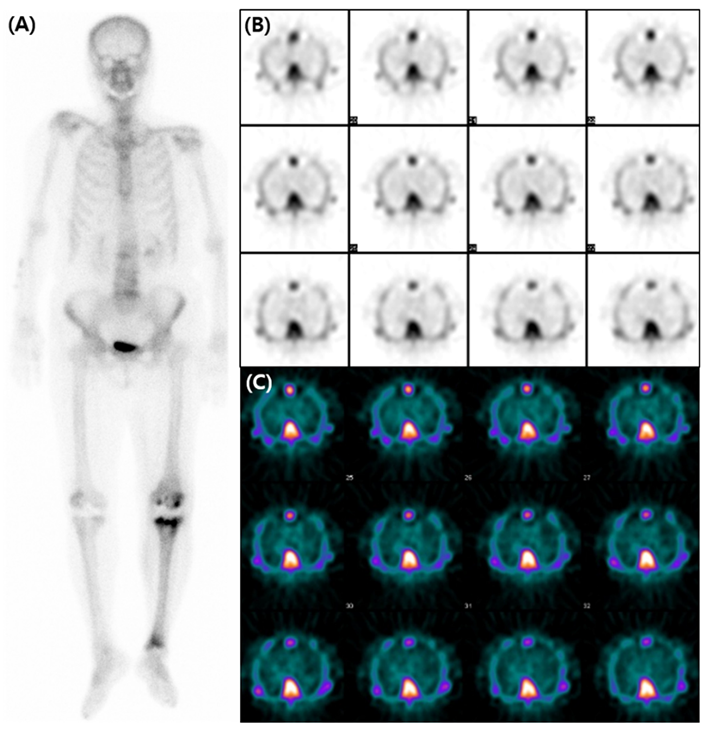

Figure 2.